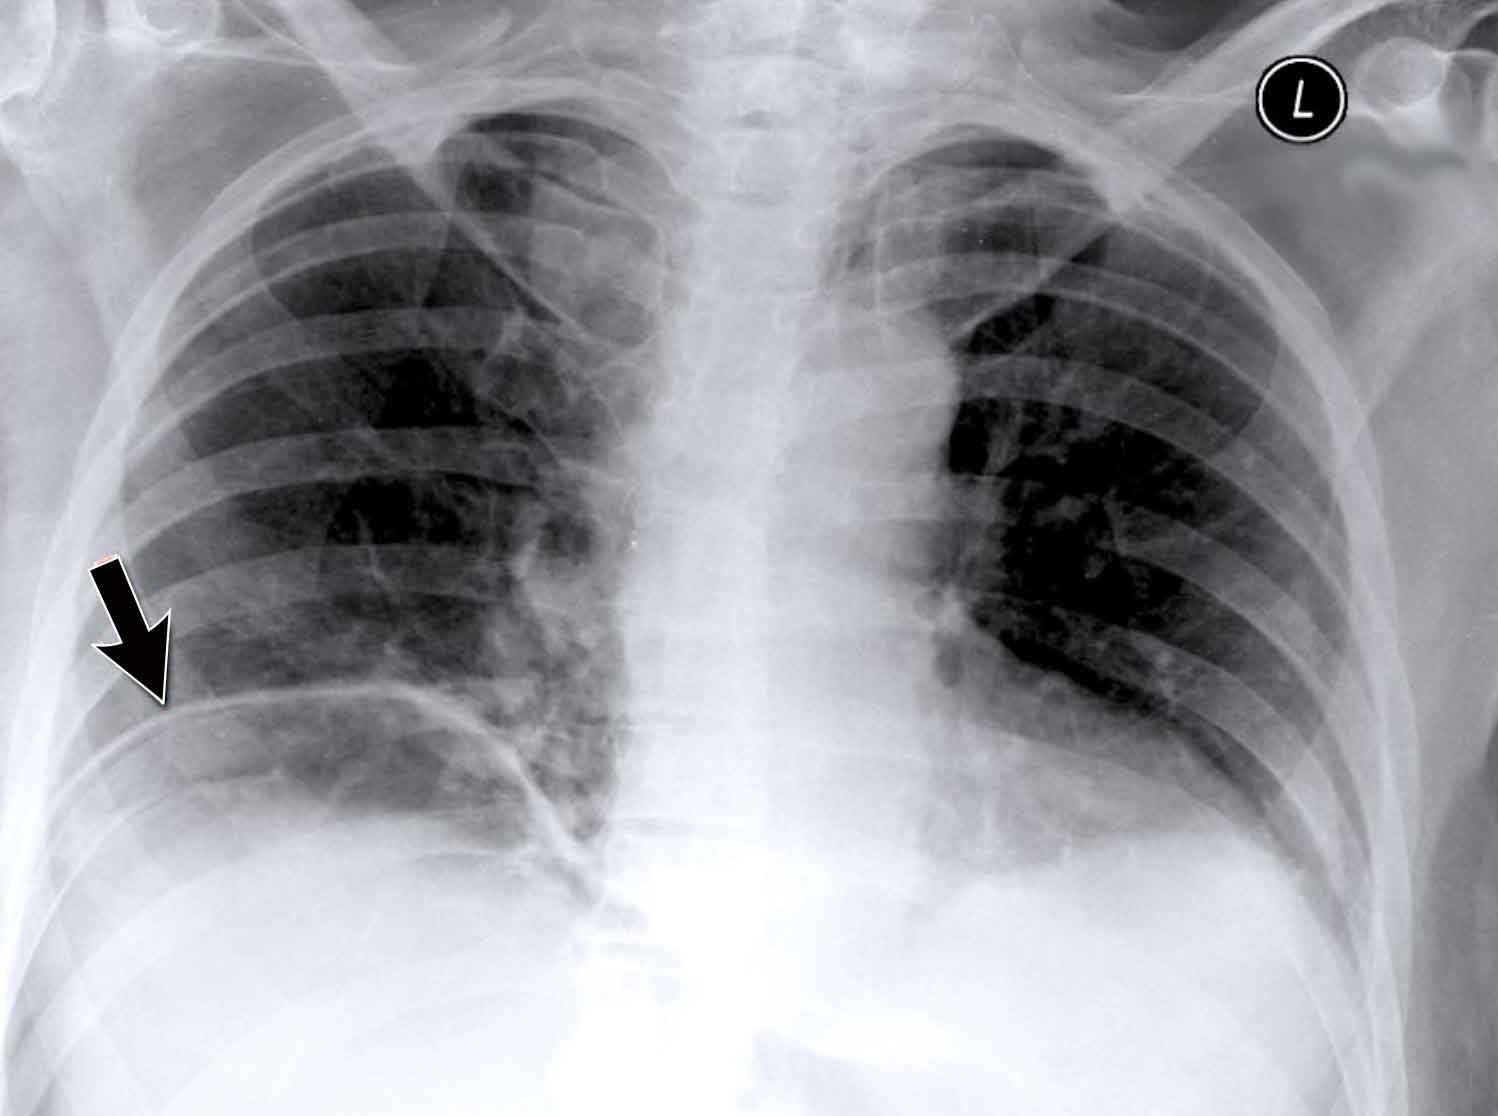

Hidden Areas (2): Right Lower Lobe Lesion

This example demonstrates a large mass in the right lower lobe that is challenging to identify on the PA view unless close attention is paid to the hidden areas.

• On initial inspection, the lesion is inconspicuous.

• However, with focused review of the subdiaphragmatic and retrocardiac regions, the abnormality becomes evident.

• Enlarge the image for better visualization.